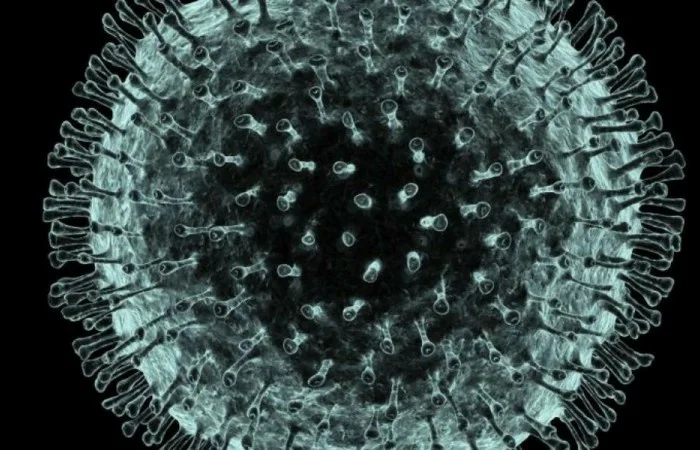

দেশে করোনায় মৃত্যু আরও ২৮ , শনাক্ত ২৭৭২

গত ২৪ ঘণ্টায় দেশে করোনাভাইরাসে আক্রান্ত হয়ে আরো ২৮ জনের মৃত্যু হয়েছে। এ মরণভাইরাসে আক্রান্ত হয়ে গতকাল ৪৮ জনের প্রাণহানি ঘটে। এ পর্যন্ত করোনায় আক্রান্ত হয়ে মোট মৃত্যুবরণ করলেন ৩১১১ জন। গত ২৪ ঘণ্টায় মৃতদের মধ্যে ২২ জন পুরুষ এবং বাকি ৬ জন নারী। গত ২৪ ঘণ্টায় নতুন করে শনাক্ত হয়েছেন ২৭৭২ জন। গতকাল শনাক্ত হয়েছিলেন ২৬৯৫ জন।

গত বছরের ডিসেম্বরের শেষ দিকে চীনের হুবেই প্রদেশের উহান থেকে করোনাভাইরাস সংক্রমণ শুরু হয়। এখন পর্যন্ত বাংলাদেশসহ বিশ্বের ২১৫টি দেশে ও অঞ্চলে ছড়িয়ে পড়েছে কোভিড-১৯।